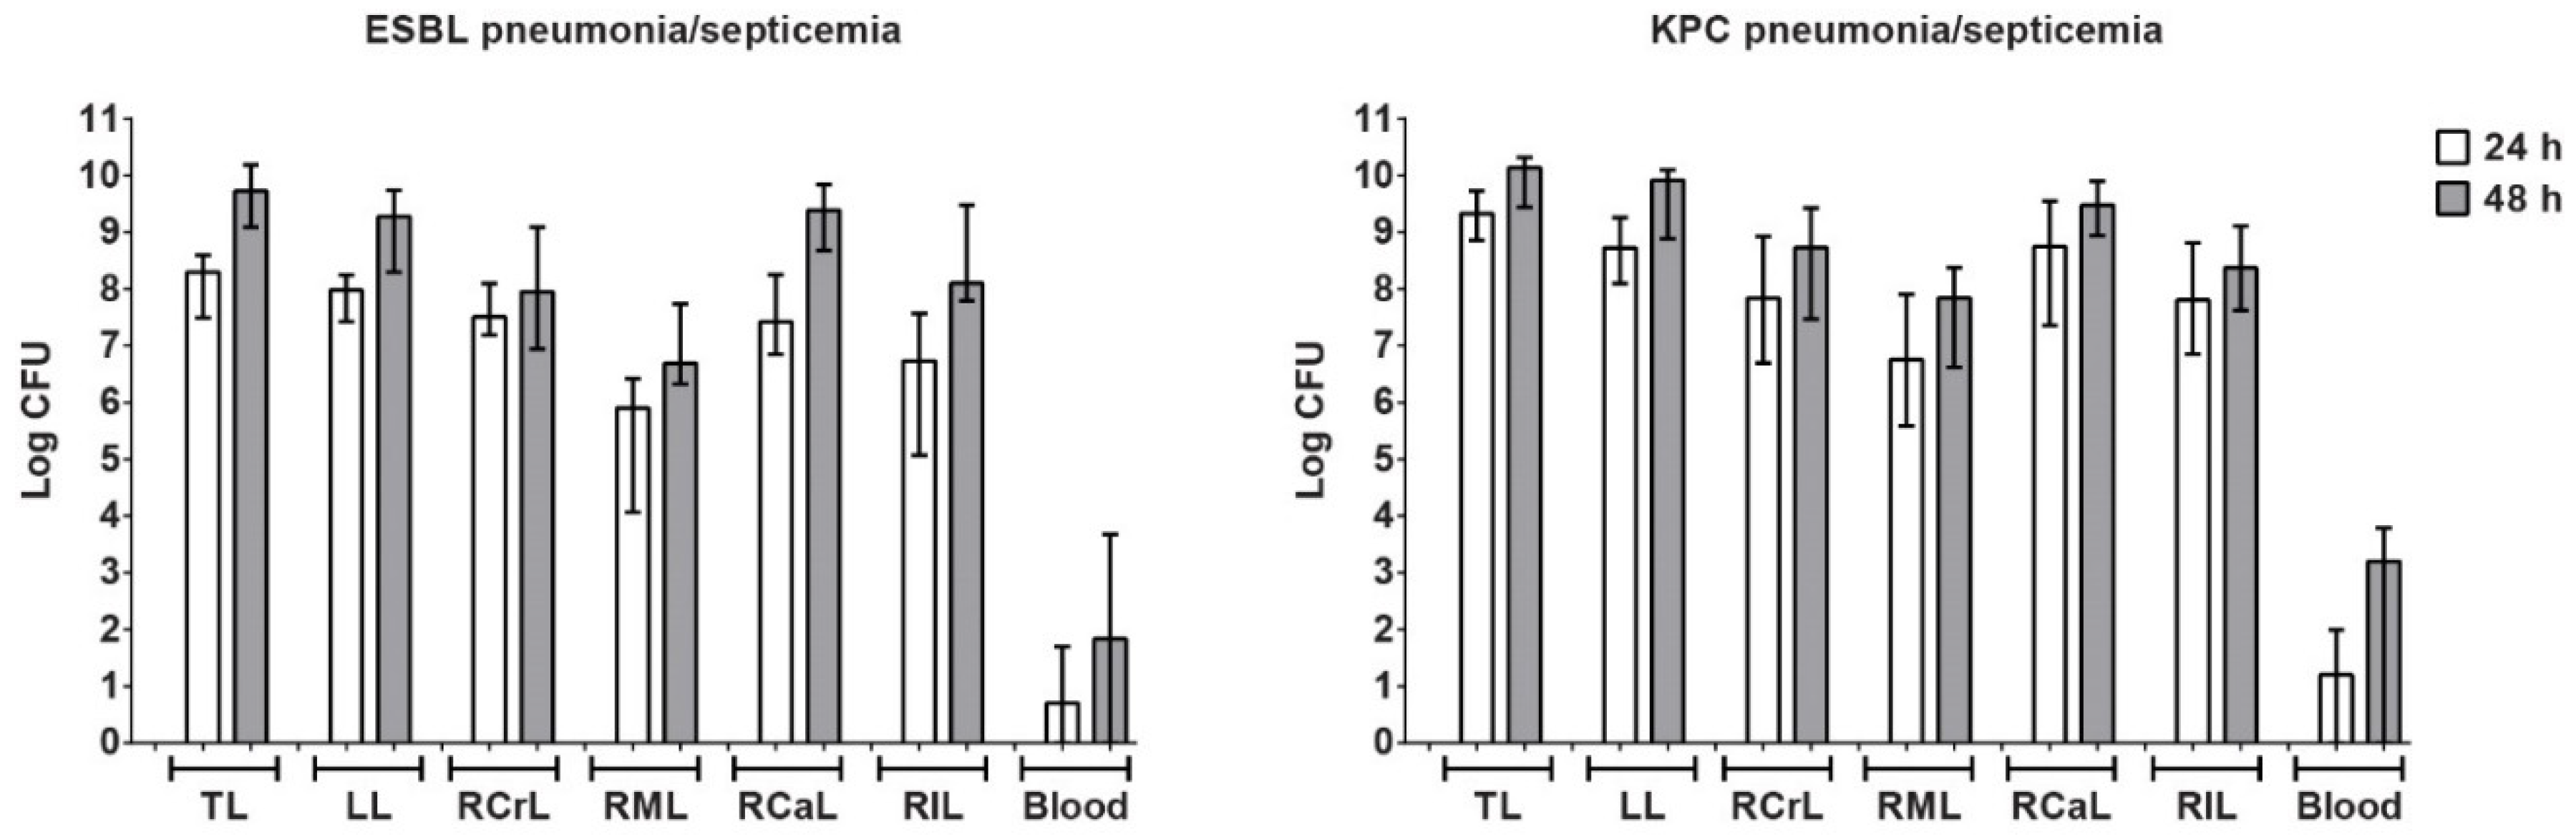

3.4. Characterization of Pneumonia–Septicemia Model